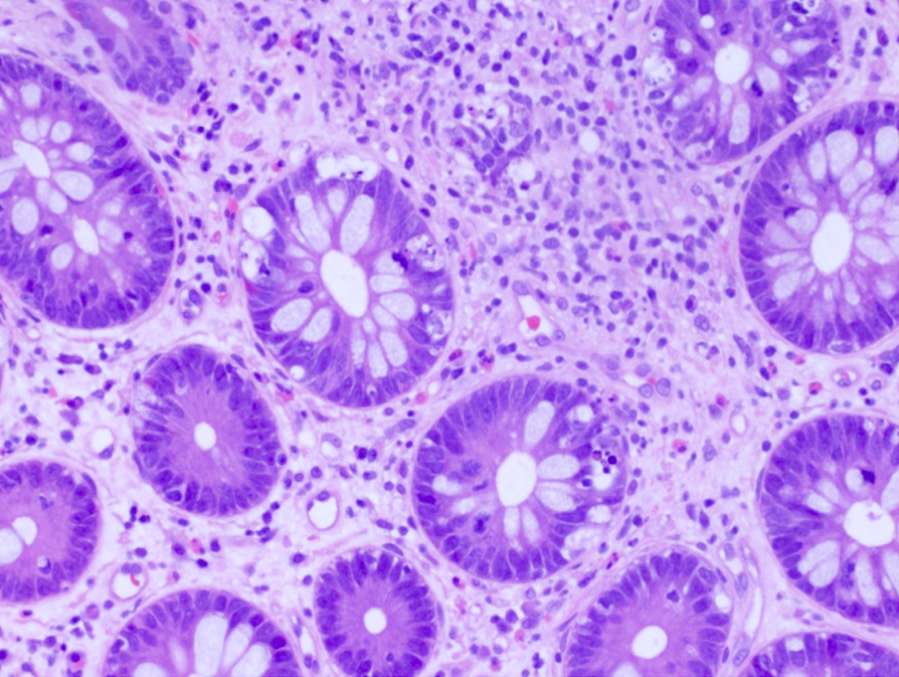

- Characteristic histologic features include crypt apoptosis, crypt dropout and ulceration (Biol Blood Marrow Transplant 2015;21:589)

- Inflammation is generally sparse

- Grade I: crypt apoptosis without crypt dropout

- Grade II: single crypt dropout

- Grade III: contiguous crypt dropout

- Grade IV: diffuse crypt dropout with ulceration